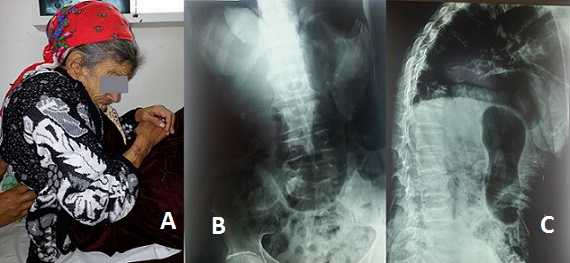

La prévalence des troubles statiques rachidiens dans les syndromes extrapyramidaux est de 13 à 90 % selon les études. Les observations de camptocormie associée à la maladie de Parkinson restent rares. Il s'agit d'un trouble postural caractérisé par une flexion du tronc qui se manifeste à la station debout et est réductible en position couchée. C'est la complication orthopédique fonctionnellement la plus grave de la maladie de Parkinson. Elle altère gravement l'autonomie, s'accompagne de désordres posturaux et correspond très probablement à une dystonie du tronc. Mme M., âgée de 71 ans, connue porteuse d'une maladie de Parkinson depuis 14 ans sous traitement avec une mauvaise observance thérapeutique, était adressée en consultation de Médecine Physique et de Réadaptation Fonctionnelle pour escarres et perte de l'autonomie. La patiente présentait des troubles posturaux du tronc, un ralentissement psychomoteur et un alitement depuis huit mois. À l'examen clinique, il était observé une inclinaison rachidienne droite avec antéflexion, une hypertonie des muscles paravertébraux droits, une bradykinésie, un visage peu expressif et une voix assourdie. La radiographie du rachis retrouvait de face une inclinaison droite sans rotation des corps vertébraux et de profil un effacement de la lordose lombaire associé à une hypercyphose dorsale. Il n'y avait pas de tassement vertébral. Le bilan biologique était normal. La constatation de ce trouble postural sans argument radiologique ou biologique pour une étiologie précise, faisait évoquer une origine extrapyramidale. L'hospitalisation a permis une amélioration des escarres mais malheureusement la patiente n'a pas repris la marche.